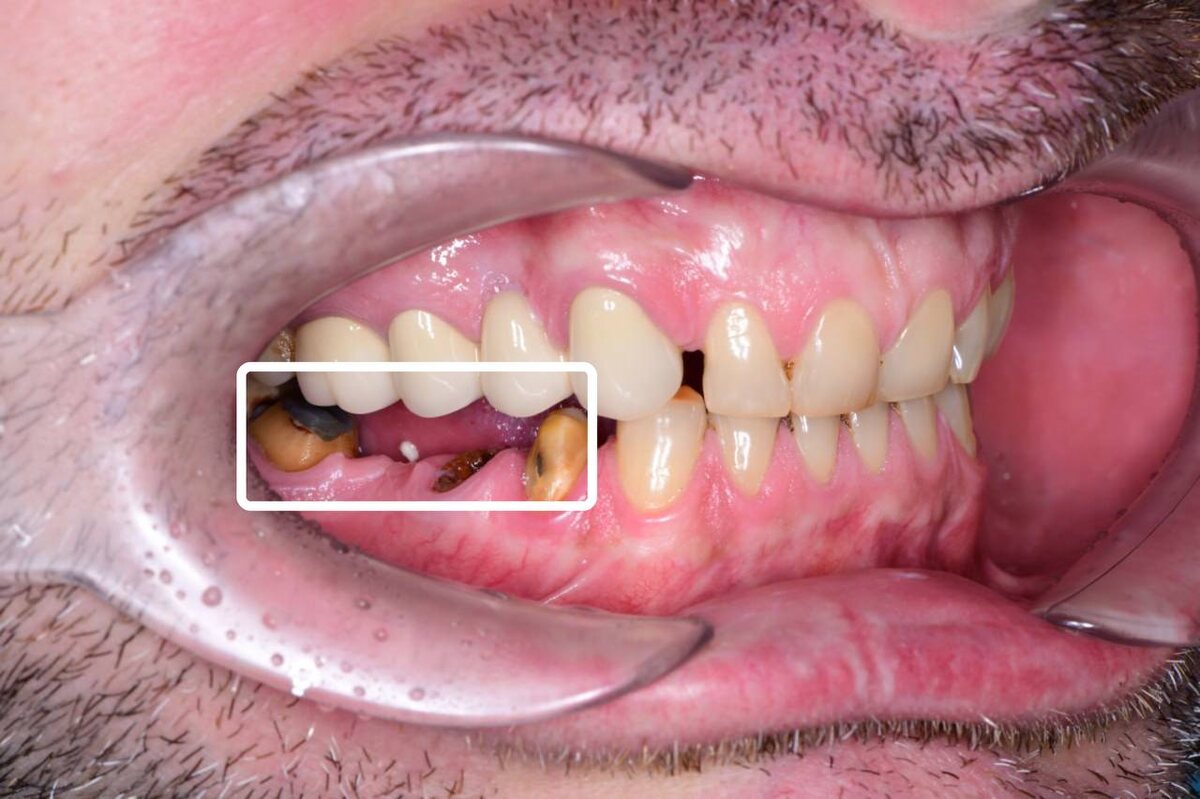

Пациент обратился с конкретной проблемой: у него слетел мостовидный протез, установленный ранее. Основной запрос — восстановление утраченного участка зубного ряда, либо путем изготовления нового моста, либо с использованием альтернативных методов.

У пациента слетел мостовидный протез

Когда начали разбираться, выяснилось, что ситуация гораздо сложнее, чем просто слетевший мостовой протез. Один из корней, на который опирался мост, оказался в сомнительном состоянии. Что с ним — не сразу было понятно, требовалось дополнительное обследование. Соседние зубы тоже выглядели подозрительно. На других зубах обнаружили старые коронки. Под ними оказалось немало неприятных сюрпризов — воспаления и разрушения.

Мы сразу же поняли, что Заур — заядлый курильщик. На зубах — плотный, желтовато-коричневый налет, особенно в пришеечной области, на задней поверхности зубов и между зубами. Это характерный признак курения: смолы и никотин из табака оседают на поверхности эмали. Пациенту объяснили, что, помимо лечения, ему необходимо регулярно проходить профессиональную чистку зубов — минимум раз в 6 месяцев.

Плотный налет из-за постоянного курения

Кроме того, у пациента так называемый глубокий прикус: верхние зубы сильно перекрывают нижние. Резцы верхней и нижней челюсти при жевании и откусывании испытывают повышенную нагрузку — и, конечно же, стираются.

У пациента глубокий прикус